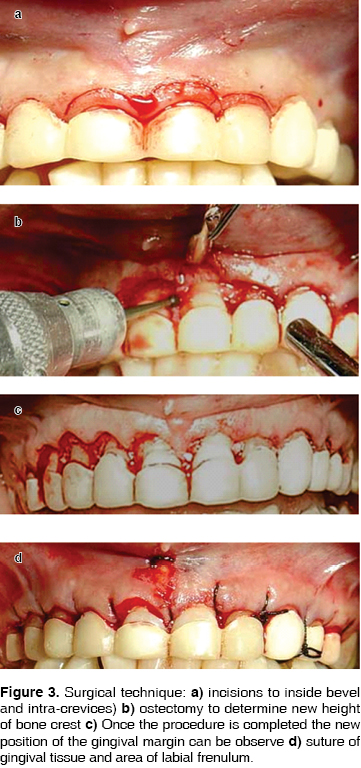

In order to determine the type of surgery to be performed (Table I) Coslet & al5 classify gingival smile as a function of the relationship established among gums, anatomical crown, cement-enamel junction (CEJ) and alveolar crest. Following these parameters they established the following types:

Type 1. The gingival margin is located in a incisive or occlusal position with respect to the cement-enamel junction. The gingival dimension of the gingival margin with respect to the muco-gingival line is acceptable. The muco-gingival line is in an apical position with respect to the alveolar crest.

Type 2. The dimension of the gingival margin to the muco-gingival line is within normal range. The muco-gingival line is at the level of the CEJ.

Sub-group a: CEJ/AC = 1.5 mm. There is normal insertion of gingival fibers to cement.

Sub group b: AC almost to the level of CEJ. Treatment plan is determined according to clinical type.